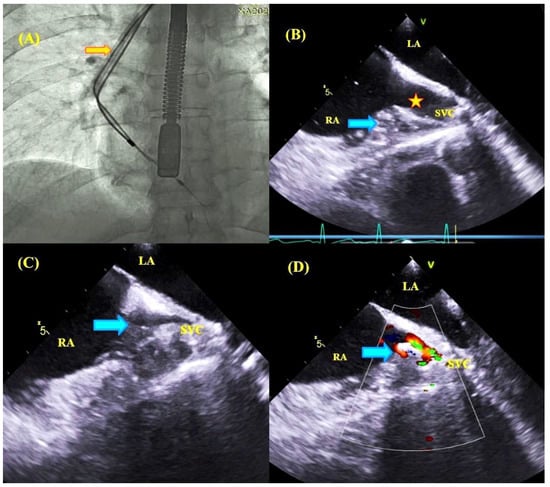

2.3. Transesophageal Echocardiographic Monitoring